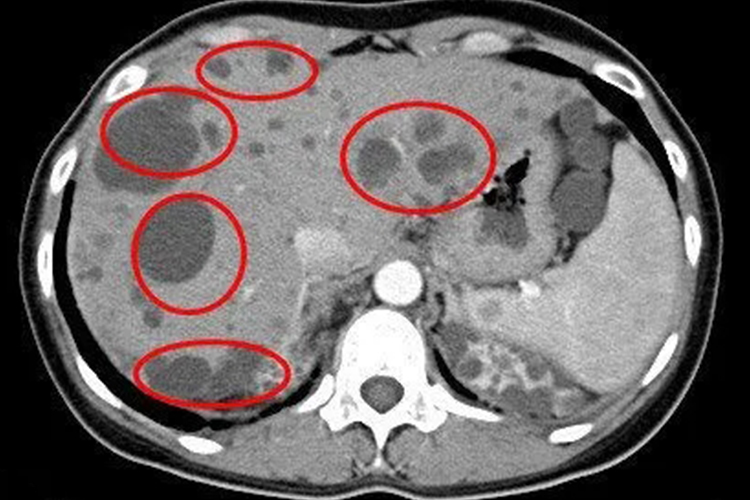

肝囊肿可通过超声检查发现,典型的肝囊肿声像图显示为圆形或卵圆形的无回声区,囊壁呈菲薄均一的强回声。其内壁光滑,外壁与周围正常肝组织界线分明,囊肿后方回声增强。小的囊肿侧壁可有浅淡的侧壁声影,有时声像图上仅显示囊肿的前壁和后壁回声。

肝囊肿一般是多发性的,单发性少见。检查发现小的肝囊肿直径数毫米,大的可占据整个肝叶,有的囊液可达10000mL以上。囊肿呈圆形或卵圆形,多数为单房性,也有呈多房性,有时还有蒂。囊肿有完整的包膜,表面呈乳白色,也有呈灰蓝色,囊壁厚薄不一,厚者可达0.5-5cm。部分患者可因此出现腹痛、食后饱涨等症状。